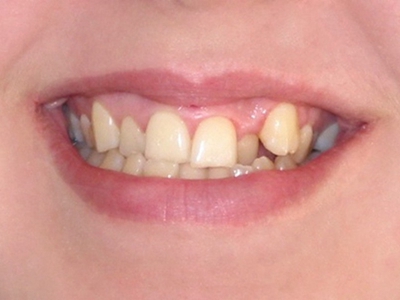

阻生牙是指由于邻牙、骨或软组织的阻碍而只能部分萌出或完全不能萌出,且以后也不能萌出的牙。引起牙阻生的成因,主要是由于颌骨缺乏足够的空间容纳全部恒牙。常见的阻生牙为下颌第三磨牙、上颌第三磨牙及上颌尖牙。

阻生牙可反复引起冠周炎,或引起邻牙牙根吸收和破坏,位置不正,不能完全萌出,好发部位是上、下颌第三磨牙。